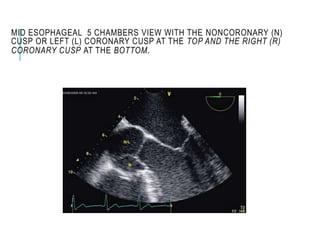

MID ESOPHAGEAL 5 CHAMBERS VIEW WITH THE NONCORONARY (N)

CUSP OR LEFT (L) CORONARY CUSP AT THE TOP AND THE RIGHT (R)

CORONARY CUSP AT THE BOTTOM.